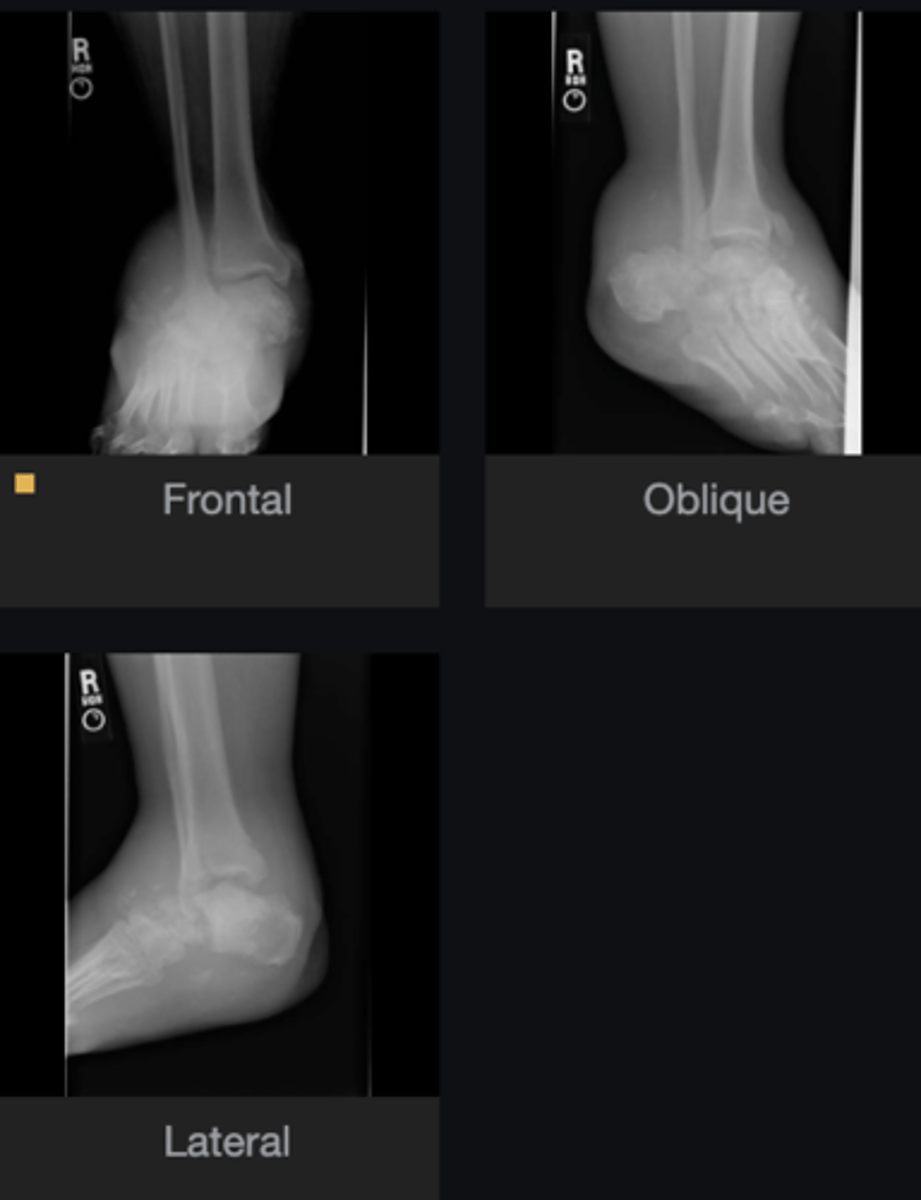

- Swelling (distension)

- Dislocation

- Destruction

- Density changes

- Debris

- Disorganization

Describe findings

- Neuropathic arthritis

- Diabetes, neurosyphilis, syringomyelia, myelomeningocele, alcoholism

- Diagnosis?

- What are some causes of this?

Primary care provider

Next step?

No

Would you adjust the ankle?